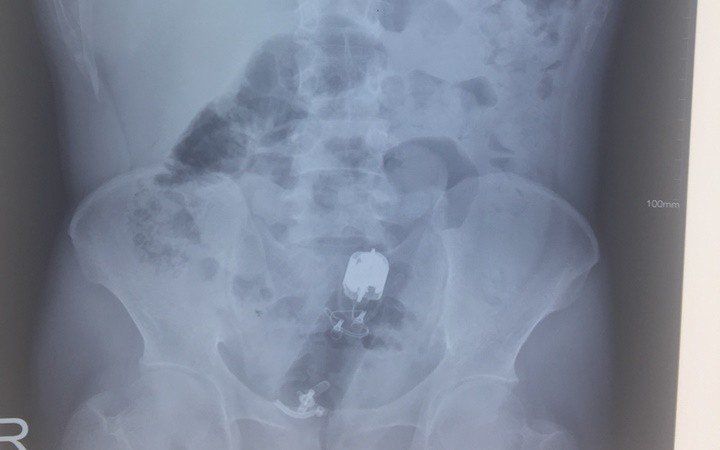

Khi chảy máu thấp mức độ nặng, có dị vật trực tràng.